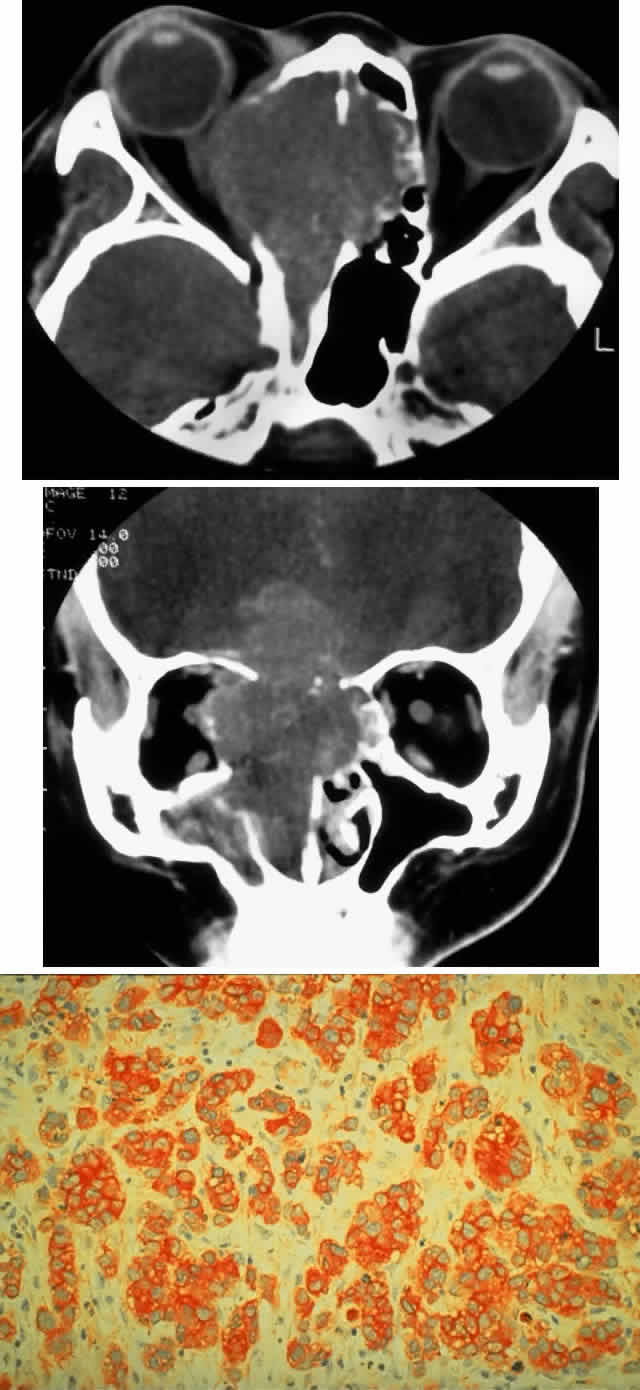

Fig. 2. A 32-year-old woman presented with a 1-month history of sinus congestion and nasal obstruction unresponsive to antibiotics. In the 1 week preceding the initial exam, the right eye became progressively more prominent and showed tearing and redness. On examination, there was mild edema of the lower lid and dysesthesia in the distribution of cranial nerve V2, and the globe was displaced 6 mm laterally and 5 mm anteriorly. There was mild limitation of abduction, chemosis, and nasal choroidal folds. An axial CT scan revealed a diffuse, destructive soft tissue mass centered in the superior nasal passage and ethmoid sinuses extending into the right orbit in contiguity with the medial rectus (A). On enhanced coronal view, the tumor was noted to involve the right maxillary antrum and to extend superiorly into the anterior cranial fossa (B). Biopsy of the sinus (C) revealed an alveolar-type rhabdomyosarcoma (muscle stain, × 320).

Fig. 3. A 73-year-old man presented with a 2-year history of infraorbital numbness and burning sensation, which had progressed to include the supraorbital region, forehead, and lower face during the past 6 months. He had been treated with radiotherapy for prostate carcinoma 7 months before orbital presentation. Examination was significant for proptosis of 2 mm and dysesthesia, including corneal numbness, in all three divisions of cranial nerve V. CT scan revealed a soft tissue mass in the inferior orbit contiguous with the inferior rectus muscle (A). The lesion extended through the infraorbital canal to involve the pterygopalatine fossa and was associated with soft tissue hanging into the upper portion of the maxillary sinus. An axial CT scan-guided aspiration biopsy was performed (B) and revealed squamous cell carcinoma. Groups of cohesive malignant squamous epithelial cells (C) were noted to have pleomorphic nuclei and abundant eosinophilic to orange cytoplasm, with no features of mucinous differentiation (H & E, × 320). (C from White VA, Rootman J: Orbital pathology. In Albert DM, Jakobiec FA (eds): Principles and Practice of Ophthalmology, Vol 4, p 2342. Philadelphia, WB Saunders, 1994.)